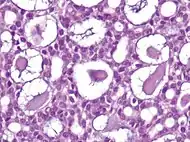

Nodular basal-cell carcinoma (also known as "classic basal-cell carcinoma") accounts for 50% of all BCC.[27] It most commonly occurs on the sun-exposed areas of the head and neck.[28]: 748 [29]: 646 Histopathology shows aggregates of basaloid cells with well-defined borders, showing a peripheral palisading of cells and one or more typical clefts.[27] Such clefts are caused by shrinkage of mucin during tissue fixation and staining.[30] Central necrosis with eosinophilic, granular features may be also present, as well as mucin. The heavy aggregates of mucin determine a cystic structure. Calcification may be also present, especially in long-standing lesions.[27] Mitotic activity is usually not so evident, but a high mitotic rate may be present in more aggressive lesions.[27] Adenoidal BCC can be classified as a variant of NBCC, characterized by basaloid cells with a reticulated configuration extending into the dermis.[27]

Cleft.

Cleft.